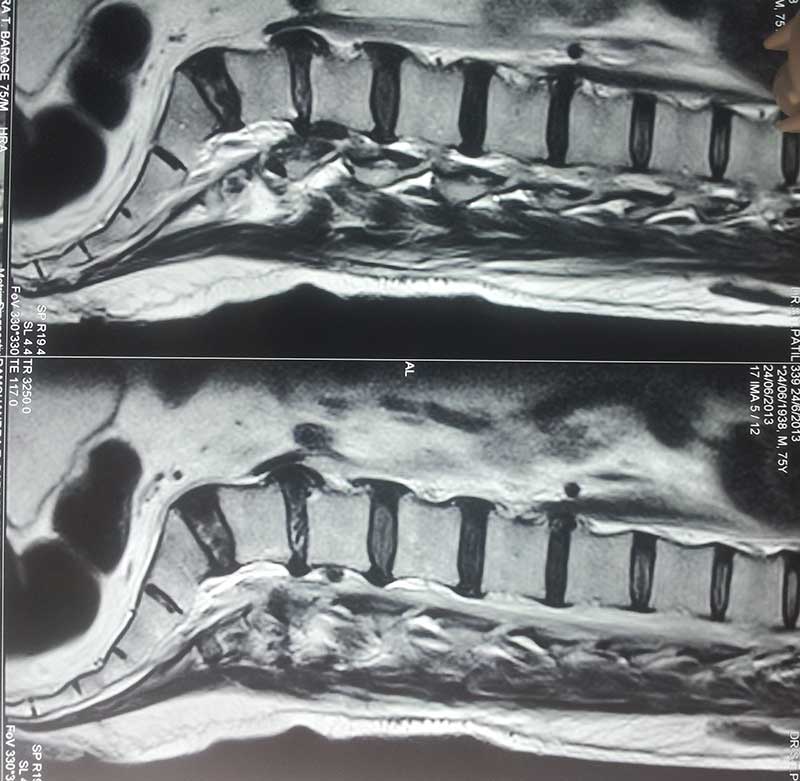

Lumber Disc Prolapse - Patient Ashok Patil